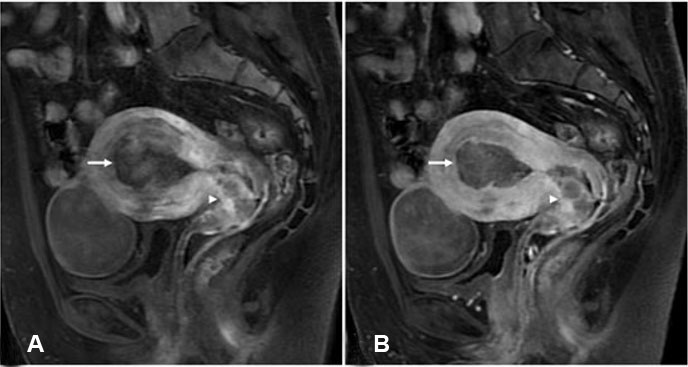

Figure 3: Contrast-enhanced magnetic resonance imaging (MRI) fat-suppressed T1-weighted images. (A) Early-phase contrast fat-suppressed T1-weighted images; sagittal section showing a stronger and more heterogeneous enhancement in the cervical mass compared with the mass in the corpus of the uterus. (B) Delay-phase contrast fat-suppressed T1-weighted images; sagittal section showing a relatively stronger heterogeneous enhancement in the cervical mass compared with the mass in the corpus of the uterus.

Retrospectively, the cervical mass showed a relatively higher signal intensity compared with the mass in the corpus of the uterus on the T2-weighted images. The cervical mass showed a stronger and more heterogeneous enhancement compared with the mass in the corpus of the uterus on the early-phase contrast fat-suppressed T1-weighted images (Figure 3A). In addition, the late-phase contrast fat-suppressed T1-weighted images showed a slight overall enhancement in the mass of the corpus of the uterus, while they showed a relatively strong heterogeneous enhancement in the cervical mass (Figure 3B). Furthermore, the constricted morphology observed in the cervix was not considered typical for invasion of endometrial cancer or cervical cancer.

Magnetic resonance imaging is a well-established method for diagnosing and staging uterine tumors, with T2-weighted imaging, diffusion-weighted imaging/ADC map imaging, and contrast-enhanced imaging now recommended [24],[25]. Endometrial carcinoma typically shows a lower signal intensity than the normal endometrium and higher signal intensity than the normal muscle layer on the T2-weighted images, as well as poor enhancement on the contrast fat-suppressed T1-weighted images [10],[11]. The uterine cancer in this case also showed these typical findings. Cervical carcinoma typically shows an early stronger enhancement compared with the surrounding stroma and myometrium [14]. The cervical cancer in this case also showed strong early enhancement, but the heterogeneous enhancement was somewhat atypical.

Because CCS is a very rare tumor, few comprehensive imaging studies have been published. However, Li et al. [26] reported that three cases of CCS showed a cervical mass with cystic and solid components with heterogeneous enhancement. They presented a mixed or low signal intensity on the T1-weighted images and a mixed or high signal intensity on the T2-weighted images. In our case, the MRI initially suggested that the CCS and endometrial adenocarcinoma appeared to be the same lesion. Retrospectively, the CCS showed an apparently stronger and more heterogeneous enhancement on the contrast fat-suppressed T1-weighted images, as well as a relatively higher signal intensity on the T2-weighted images and lower ADC value compared with the endometrial adenocarcinoma. It is unclear why the CCS showed a higher signal intensity on the T2-weighted images and lower ADC value. However, the CCS showed heterogeneous enhancement potentially because it contained multiple different components.